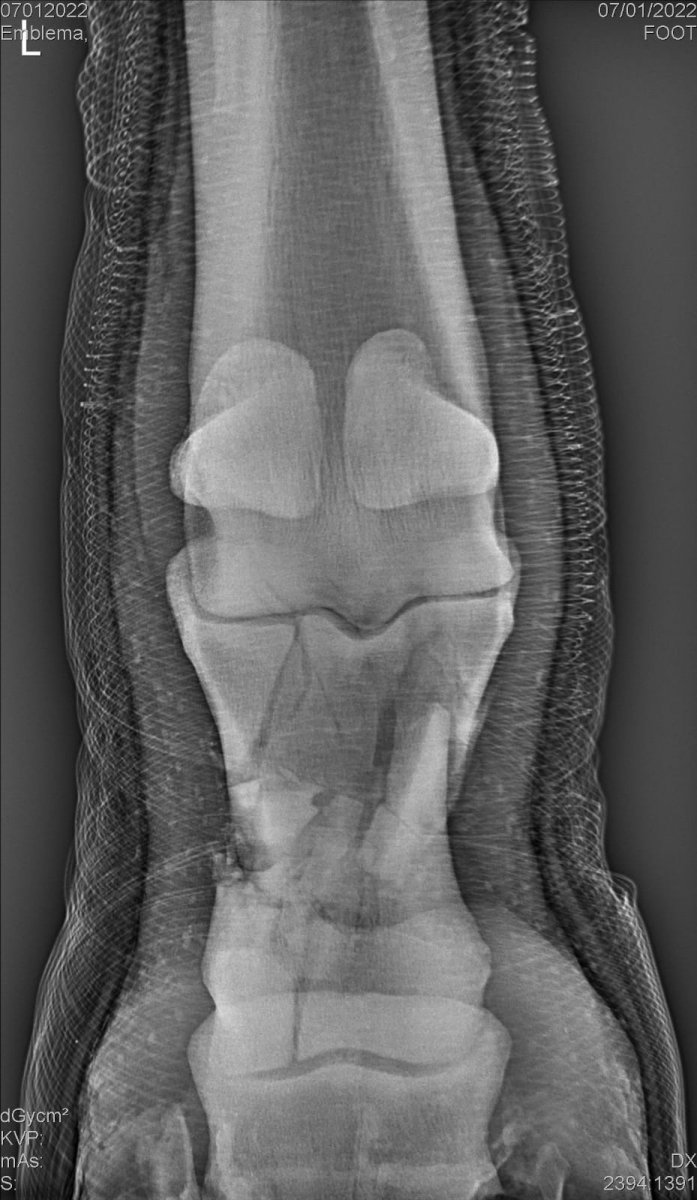

Кобыла два дня назад получила перелом при работе на корде. Кобыле 21 год. Кто с таким сталкивался? Возможно ли восстановить лошадь в качестве газонокосилки? На данный момент кобыла в гипсе, температура в норме, аппетит хороший, делаем массаж здоровых конечностей.

Вот такой был перелом и как он сросся через 6 месяцев

Полгода простоял в гипсе, меняли гипс через три месяца, потом ещё два месяца и один месяц в утягивающей повязке. Перелом был в июле, первый раз конь вышел из денника в декабре. Тяжелые были полгода, ему было тяжело самостоятельно вставать с гипсом, рекомендую положить резиновый пол в денник, чтобы ноги не скользили. Плюс он бился головой об поилку, перевесили ее в дальний угол денника. Очень сильно похудел, но в этот период много кормить нельзя, потому что лишний вес даёт нагрузку на здоровые ноги. Ел сено и гранулы без овса либо мэш. Обязательно кальций давать.

Вторая задняя нога сильно компенсировала поломанную, расчищать не могли толком, и там образовался небольшой ламинит в итоге. Перелом полностью сросся, но кость просела немного, поэтому ходит он не очень ровно. В остальном больше проблема со второй ногой, приходится делать ковку на зада, иначе сразу начинает хромать сильно.